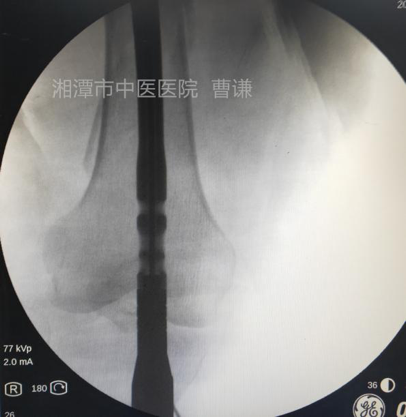

在远折端依前法再置入一根钢丝进行捆扎复位,因担心过度拧紧导致钢丝断裂,没有强求骨折解剖复位。

追求完美者可以将钢丝再拧紧一些,复位将更漂亮。